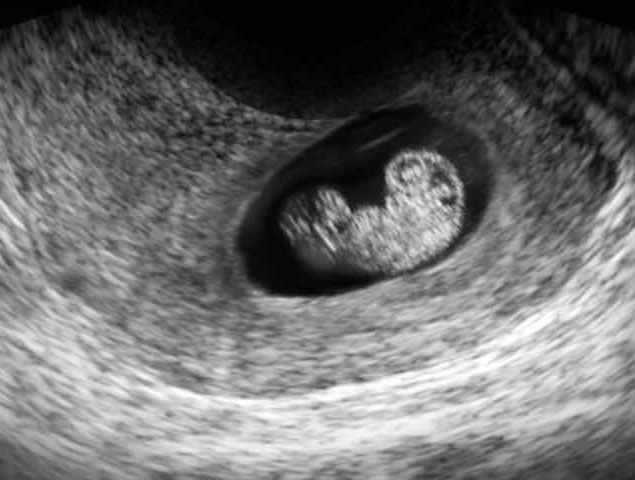

7 неделя беременности - это середина 2-го месяца. Вы уже можете начать ощущать характерные симптомы - тошноту и рвоту, хотя у многих женщин преобладают сонливость и утомляемость. Время для первого визита к гинекологу. Зародыш еще небольшой - около 4-5 мм, но быстро развивается.

7 неделя беременности - момент, когда голова ребенка развивается исключительно хорошо. Если бы вы могли посмотреть на него под микроскопом, вы бы увидели, что он уже имеет правильную форму и все больше и больше деталей.

пятна медленно превращаются в глазные яблоки, также можно увидеть дырочки, которые вскоре превратятся в ноздри. Также видны зачатки языка, рта и зубов. Руки и ноги значительно вырастают, а на их концах есть семена для рук и ног. Сердце разделено на правый и левый желудочки, и оно бьется четко и быстро - примерно в два раза быстрее вашего. У ребенка уже сформирован скелет, хотя пока он состоит только из мягких хрящей. Внутренние органы все еще развиваются, особенно пищеварительная система - кишечник и печень, но также и внутренние половые органы - у мальчика формируются пенис и яички, а у девочки - яичники. Хотя эти органы уже формируются, снаружи их не видно, поэтому на УЗИ определить пол ребенка не представляется возможным .